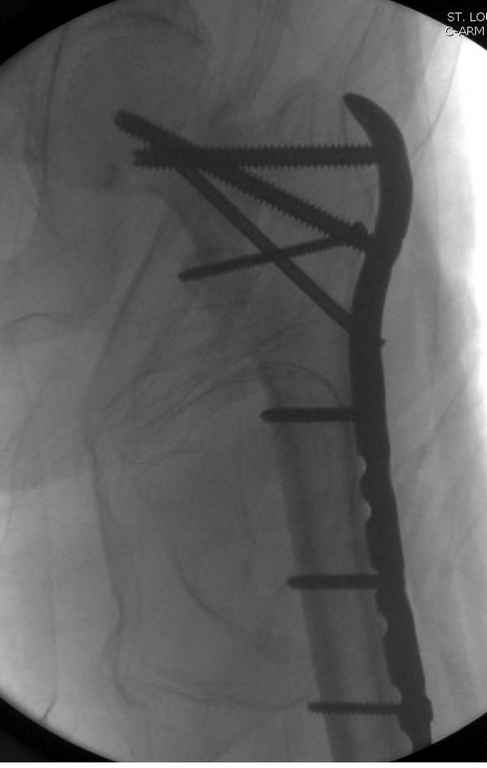

Re: оскольчатый чрезвертельный перелом

А так для лечения оскольчатых переломов подходят все методы, включая интра- и экстрамедуллярные в зависимости от опыта и наличия импланта.

Здесь пара похожих случаев.